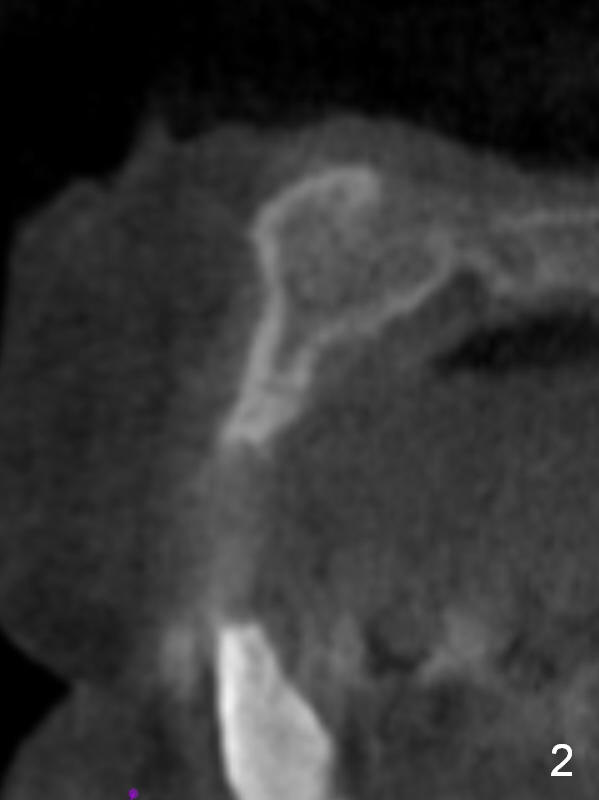

After implant reconstruction of the lower right and left (including #19) regions, the same treatment is considered in the atrophic anterior maxilla (#8-13) for anchorage for upper left molar cross bite correction. The smallest implants are to be placed in the each of the sites with different strategies. For example, at the site of #8 (Fig,1,2), ridge split with wheel (Fig.3) and microsteotomes (Fig.4) are used to place 1-piece implant (3x14 mm). The site of #9 has a pointed ridge and a wide base (Fig.6); a 1-piece angled implant (3x14 mm 15 °) is placed palatally (Fig.7). The ridge and base at #10 are narrow (Fig.8); after truncating the pointed ridge, a 2.0 or 2.5 mm 1-piece implant is placed parallel to the palatal wall (Fig.9).